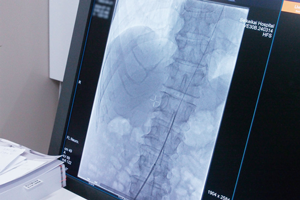

最新鋭の血管撮影装置

2024年7月、最新鋭の血管撮影装置「ARTIS icono D-Spin」を導入しました。この装置は従来の血管撮影装置と比較し患部撮影画像の精密さ、動作スピード、操作性が特に優れています。

血管内治療において治療時間の短さや緻密さ・正確さは最も重要な部分です。経験豊富な脳血管内治療専門医がこの「ARTIS icono D-Spin」を使い治療をおこなうことで、これまで以上に安全・安心かつ質の高い医療の提供が可能になります。

導入後のメリット・治療の質・安全性の向上

短時間での高精密画像と3D撮影が可能となったことで、頭蓋骨内の状態変化を細部まで鮮明に確認しながら処置を行うことができます。

これらの技術を用いた画像撮影時間の大幅な短縮は撮影時の患者さんの負担の軽減し、放射線被ばく量の低減へと繋がります。

附属の補助機能(アプリ)の充実

動脈瘤のサイズや血管の測定など、様々なアプリが登載されており、それらを駆使することで治療の精度、安全性、スピードが向上。より質の高い救急医療の提供が可能になりました。